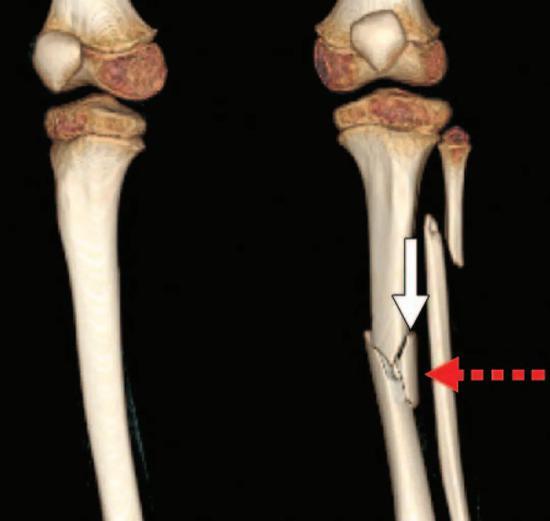

在法医的实际工作中,虚拟尸检的优势还表现在对骨折损伤、心脑血管病变和各类栓塞的检验上。解剖中对骨折部位的探查是一项重要任务,高坠、车祸等案例中复杂的骨折往往会产生较多的骨碎片,切开探查很容易使骨碎片发生位移,往往很难掌握骨折的原始位置关系,对骨折成因的评估难度也会增加。而虚拟尸检无须切开探查就可以确认全部的骨碎片、评估导致骨折的力的方向。甚至可以说,骨折越复杂,虚拟尸检在分析其成因上的优势就越明显。

虚拟尸检评估交通事故中行人的左胫骨、腓骨骨折,红色箭头为作用力的方向。